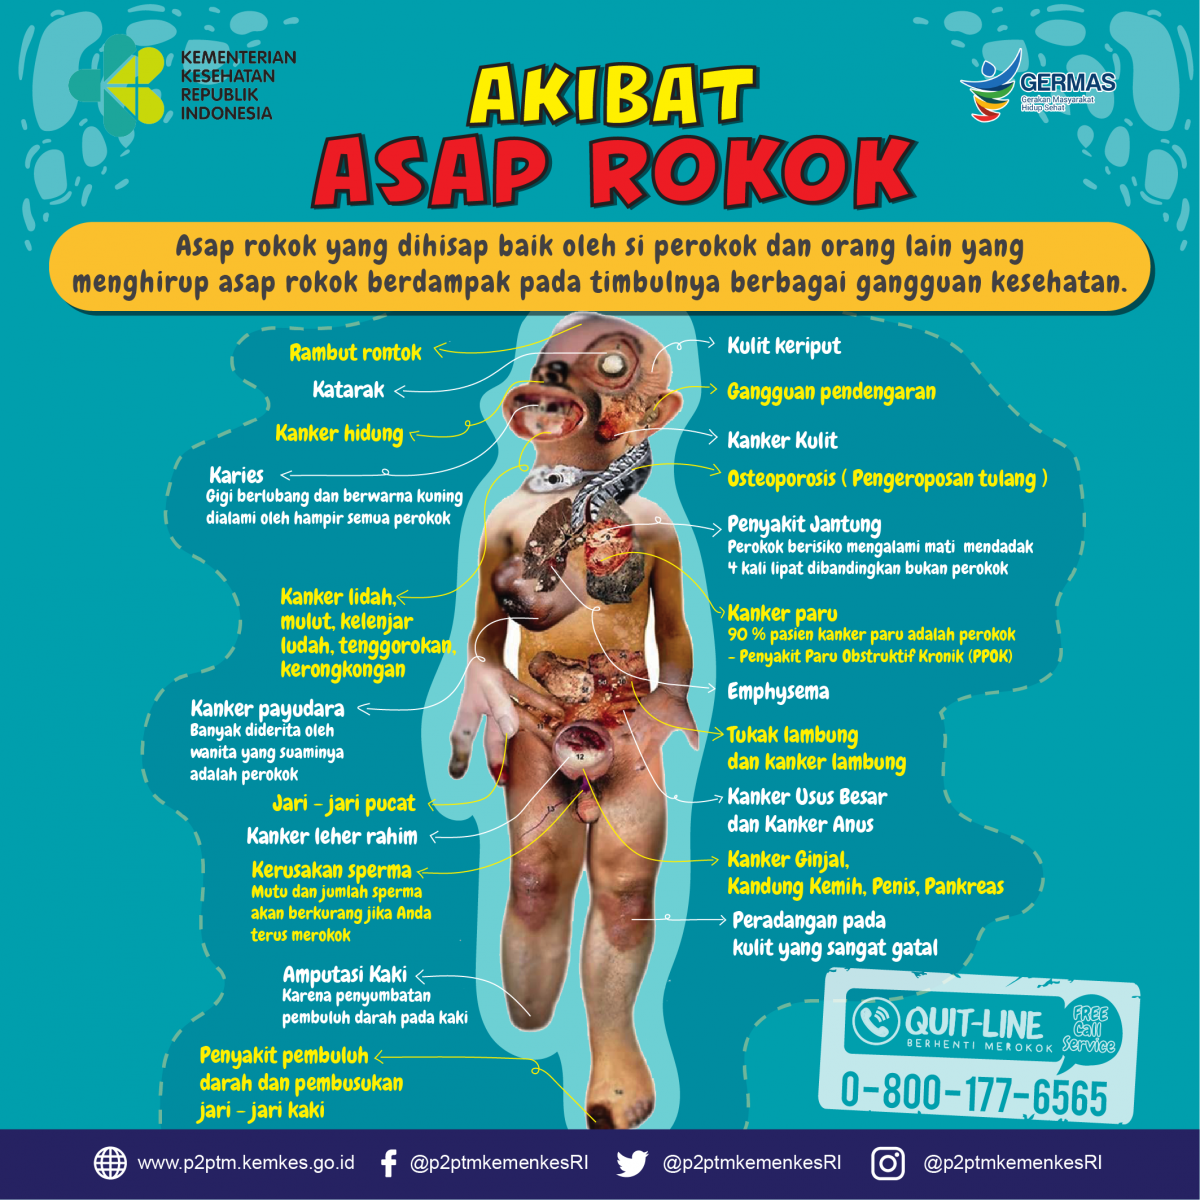

Asap Rokok Berdampak Pada Timbulnya Berbagai Gangguan Kesehatan Yuk Simak Gambaran Berikut Direktorat P2ptm

Asap Rokok Berdampak Pada Timbulnya Berbagai Gangguan Kesehatan Yuk Simak Gambaran Berikut Direktorat P2ptm

Akibat Asap Rokok Direktorat P2ptm

Akibat Asap Rokok Direktorat P2ptm

Gambaran Akibat Asap Rokok Direktorat P2ptm

Gambaran Akibat Asap Rokok Direktorat P2ptm

Akibat Asap Rokok Direktorat P2ptm

Akibat Asap Rokok Direktorat P2ptm

Apa Saja Akibat Asap Rokok Direktorat P2ptm

Apa Saja Akibat Asap Rokok Direktorat P2ptm

Gambaran Akibat Asap Rokok Direktorat P2ptm

Gambaran Akibat Asap Rokok Direktorat P2ptm